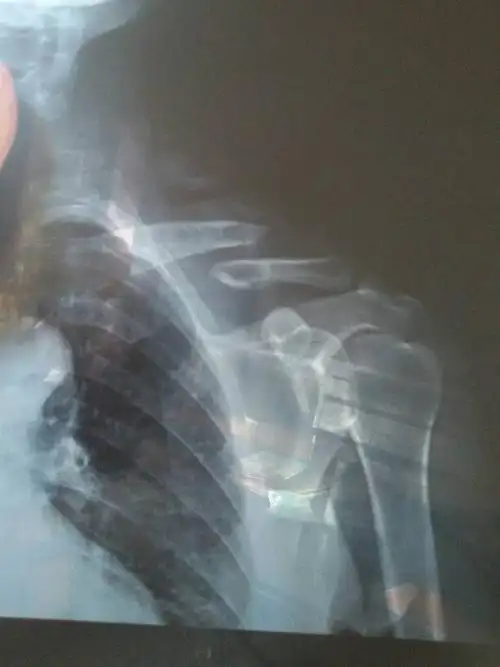

问:左锁骨外1/3段骨折,有x光片,请问是否可以保守治疗?